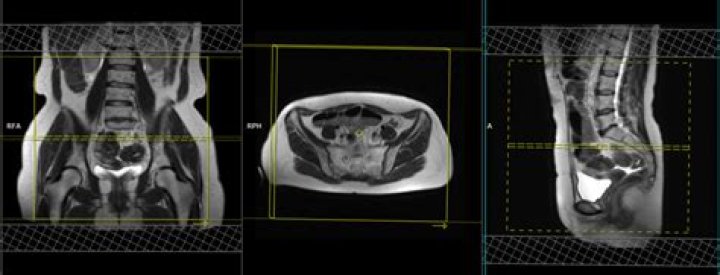

Pelvic magnetic resonance imaging (MRI) is one imaging technique that doctors may use to help diagnose endometriosis. The test provides a picture of organs inside the pelvic cavity and shows endometrial growths that may require further investigation.

Currently, MRI is considered the best imaging technique for mapping endometriosis, since it provides a more reliable map of deep infiltrating endometriosis than physical examination and transvaginal ultrasound (TVUS) [8].

A pelvic MRI is the best imaging technique for preoperative staging of endometriosis. Compared with an ultrasound, it provides a more reliable picture of deep, infiltrating lesions that require further investigation.